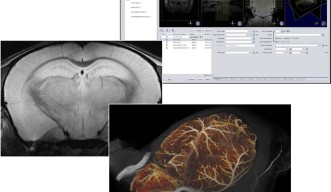

この度OISTでは、小動物における生体の代謝や機能といった高度な生体情報の解析を可能にする、小動物用核磁気共鳴イメージングシステムを導入し、施設の運用準備を開始しました。解像度の高さを決める静磁場強度において、最高レベルの性能を持つ同システムの導入は、国内において本学が2例目です。現在、システム利用に向けて学内での調整を進めており、将来的には学外機関の研究活動にも寄与するものと期待されます。

臨床画像診断で広く用いられている核磁気共鳴撮像(MRI)は、生体を傷つけることなく、内部を可視化する診断機器の一つです。MRIは、主に生体内の水素原子核の磁気共鳴現象を捉えます。磁気共鳴現象とは、磁場の中で原子核が特定の周波数の電磁波と共鳴を起こす現象のことを指します。MRIでは、この共鳴によって生じる電磁波の強度と周波数を基に物質の違いを画像化します。そのため脳や内臓、筋肉など、水素原子を多く含む水が豊富な領域において、鮮明な画像が得られ、脳腫瘍や脳梗塞の検出に優れています。画像の元となる電磁波の強度は、用いる静磁場の強さ(テスラ)にほぼ比例し、得られる情報量に大きく影響します。医療用としては1.5テスラのMRIが広く普及していますが、本システムは、11.7テスラという国内最大磁場強度を誇り、極めて多くの情報を得ることができます。そのため、本システムはマウスなどの小型の動物においても、形態情報のみならず、代謝や機能に至る様々な生体情報の解析に優れた性能を発揮します。

システムの導入に尽力した、山本雅教授の細胞シグナルユニットは、マウスモデルを用い、がん、神経疾患、免疫疾患、および糖尿病や肥満のメカニズムを分子レベルで解明することを目標としています。そして本システムを用いることで、特定の遺伝子に変異をもつマウスの体内で、実際にどのような変化が起こっているのか、同一個体において繰り返し、長期的にその変化を追うことが可能となります。